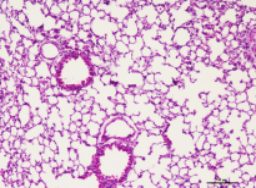

2.1HE检测